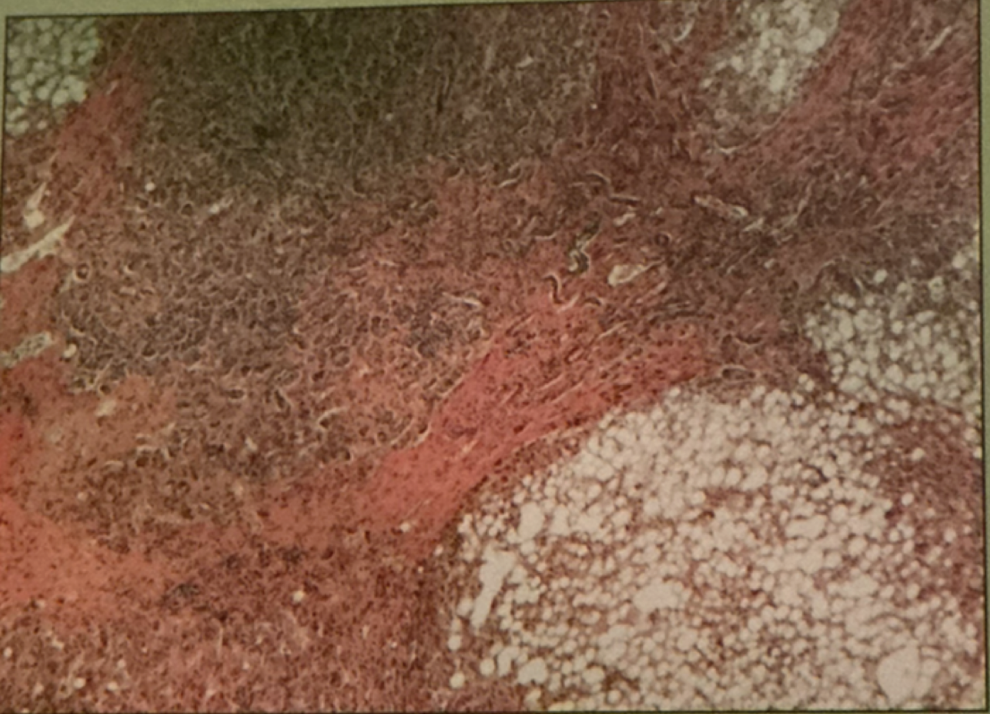

hodgkin’s granuloma

hodgkin’s granuloma

cancer of lymph system - breakdown of red and white pulp

reed-sternberg cells